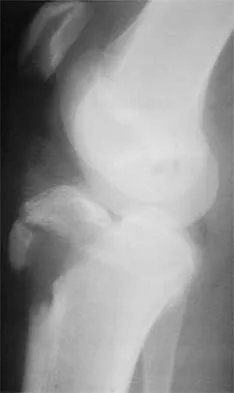

Figure 35 shows the lateral radiograph of a 15-year-old basketball player who felt a dramatic pop in his knee when landing after a lay-up. The patient reports that he cannot bear weight on the injured extremity. Management should consist of

Explanation